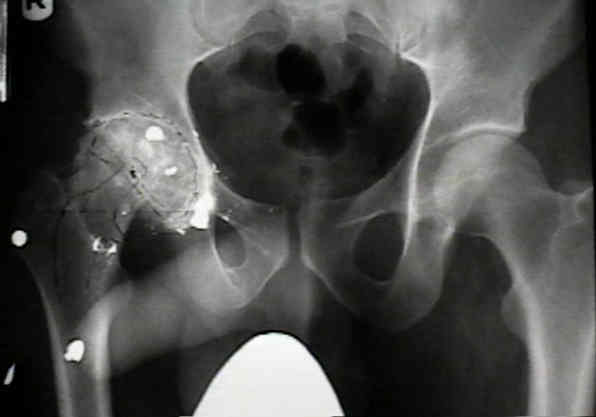

Case Example

- 35-year-old male w/ near anklyosed hip following a GSW to the hip;

- preoperative films appeared to indicate that little or no medialization was necessary;

- postoperative films, however, indicate that the cup was lateralized (hence, reaming was inadequate);

- in retrospect, the radiographs which are rotated externally (like an iliac oblique) tend to falsely minimize the necessary amount of medialization where as X-rays which are rotated internally (like an obturator oblique), tend to over-estimate the necessary amount of medialization